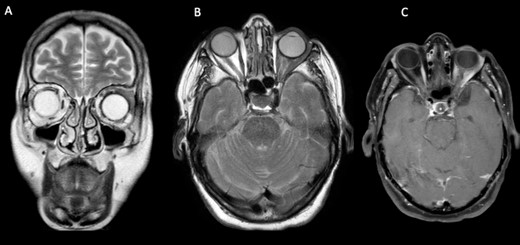

The CT scan displayed a tissue infiltration and bulking of the left superior and lateral extraocular rectus muscle (Fig. 1).

Axial and coronal cerebral CT scans show enlargement of the left lateral and superior rectal muscles (A–B), with slight enhancement (C–D).